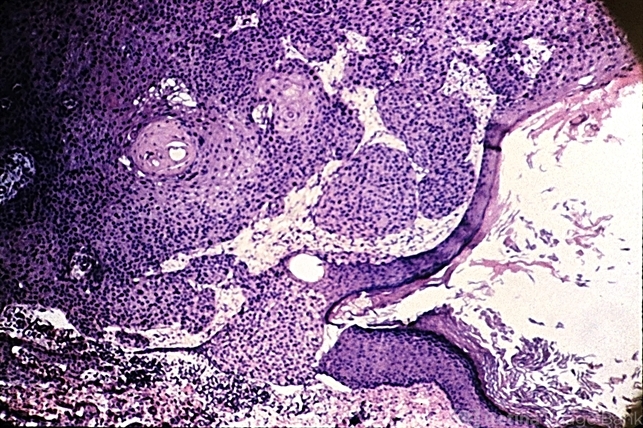

- epithelium, squamous cells

- Edge of squamous cell carcinoma of the skin showing sudden change from normal epithelium to infiltrating islands of large, malignant squamous cells.